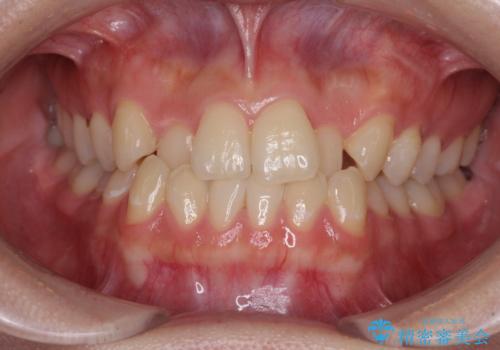

【モニター】八重歯と前歯のクロスバイト ワイヤーを併用しインビザラインで矯正治療